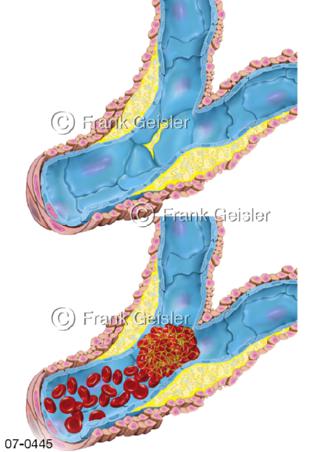

Bilder zu Herz, ein muskuläres Hohlorgan, das den menschlichen Körper durch rhythmische Kontraktionen mit Blut versorgt und dadurch die Durchblutung der Organe sichert, das Kreislaufsystem zeigt den Transport von arteriellem sowie venösem Blut durch das kardiovaskuläre System (Herz-Kreislauf-System), bestehend aus Blutgefäßen, Lymphgefäßen und dem Herz